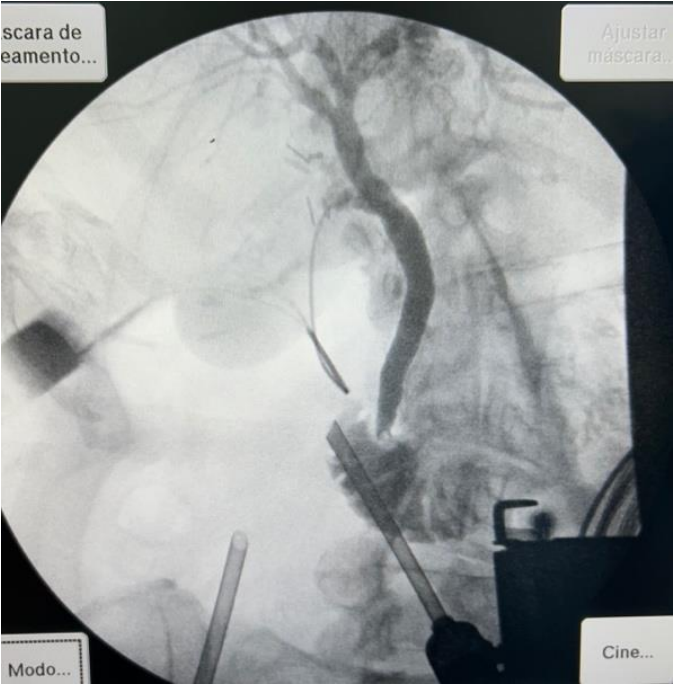

Uma paciente de 73 anos apresentou dor abdominal no hipocôndrio direito há seis dias, associada a mudança no padrão alimentar e perda de peso. Ao dar entrada no pronto-socorro, os exames laboratoriais mostraram os seguintes resultados: Hemoglobina 12,3 g/dL, leucócitos 12.630/mm³, bilirrubina total 1,3 mg/dL, bilirrubina direta 0,94 mg/dL, INR 1,0, fosfatase alcalina 215 U/L, GGT 748 U/L, amilase 97 U/L, ALT (TGP) 676 U/L, AST (TGO) 349 U/L, PCR 13,7 mg/L (VR<1,0), ureia 50 mg/dL e creatinina 1,25 mg/dL.

Foi submetida à colecistectomia videolaparoscópica e optou-se por realizar uma colangiografia intraoperatória que resultou na imagem a seguir.

Assinale a alternativa que corresponde ao diagnóstico encontrado: